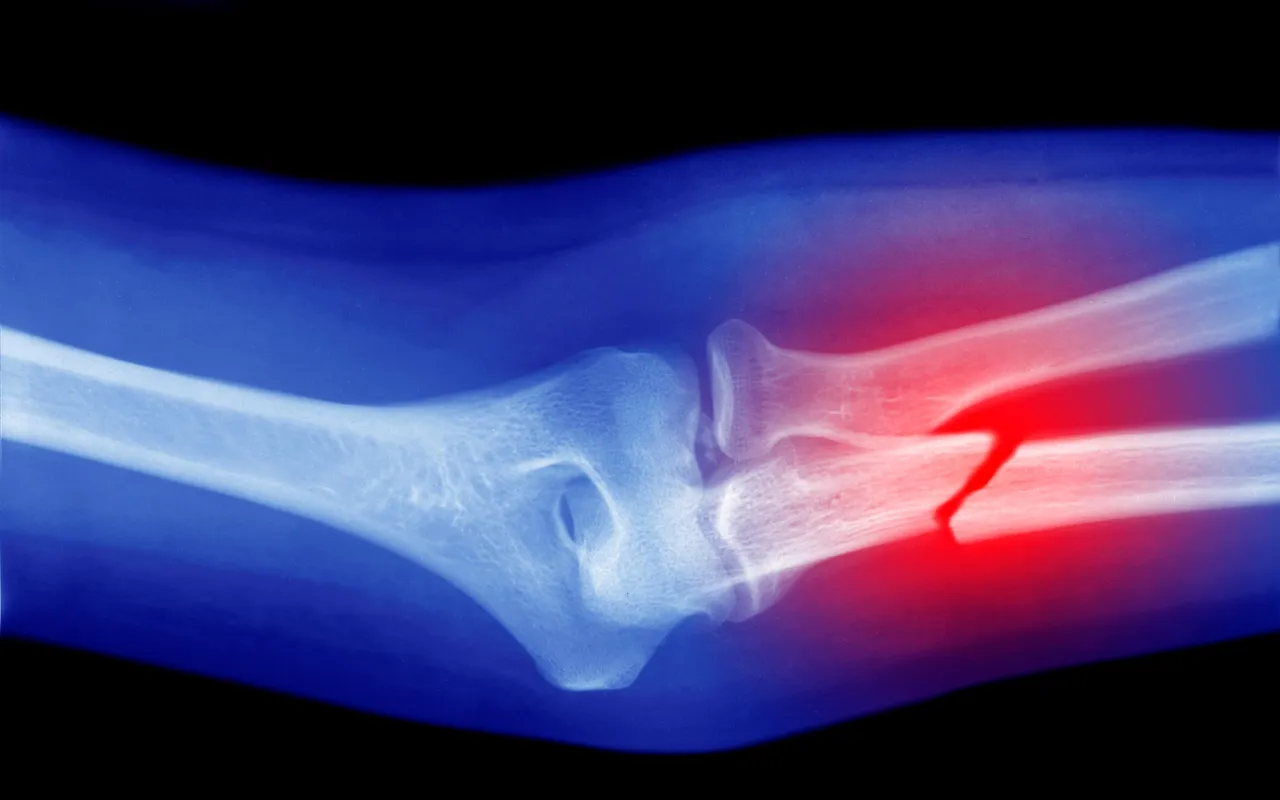

Ao longo da vida, seus ossos são repostos. A osteoporose é uma condição em que esse processo não ocorre corretamente, com a degradação óssea ultrapassando a taxa de sua reposição. Isso leva ao enfraquecimento dos ossos ao longo do tempo e à maior probabilidade de fraturas. A condição tem muitos fatores de risco — idade, sexo, medicamentos, dieta, tabagismo, consumo de álcool e fatores genéticos —, com a doença se desenvolvendo lentamente ao longo do tempo. Muitas vezes, as pessoas só percebem que têm a doença quando quebram um osso.

Esta nova análise, publicada na revista Osteoporosis International, acrescenta a exposição a microplásticos como um potencial novo fator de risco. A pesquisa revisou 62 artigos científicos que realizaram diversos testes em laboratório e em animais sobre os possíveis efeitos de micro e nanoplásticos nos ossos. A análise de experimentos laboratoriais mostrou que os microplásticos estimulam a formação de osteoclastos, células criadas por células-tronco na medula óssea que degradam o tecido ósseo para promover a reabsorção, o processo no qual o corpo decompõe e elimina ossos velhos ou danificados.

O estudo também constatou que, em relação aos ossos, as partículas plásticas podem reduzir a viabilidade das células, induzir o envelhecimento celular prematuro, modificar a expressão genética e desencadear respostas inflamatórias. A combinação desses efeitos gera um desequilíbrio no qual os osteoclastos destroem mais tecido ósseo do que regeneram, causando um enfraquecimento acelerado da estrutura óssea.

Ao analisar estudos em animais, os pesquisadores descobriram que o acúmulo de microplásticos no corpo diminui a contagem de glóbulos brancos — o que sugere alterações na função da medula óssea. Além disso, esses estudos em animais sugeriram que o impacto dos microplásticos nos osteoclastos pode estar associado à deterioração da microestrutura óssea e à formação de estruturas celulares irregulares, aumentando o risco de fragilidade óssea, deformidades e fraturas.